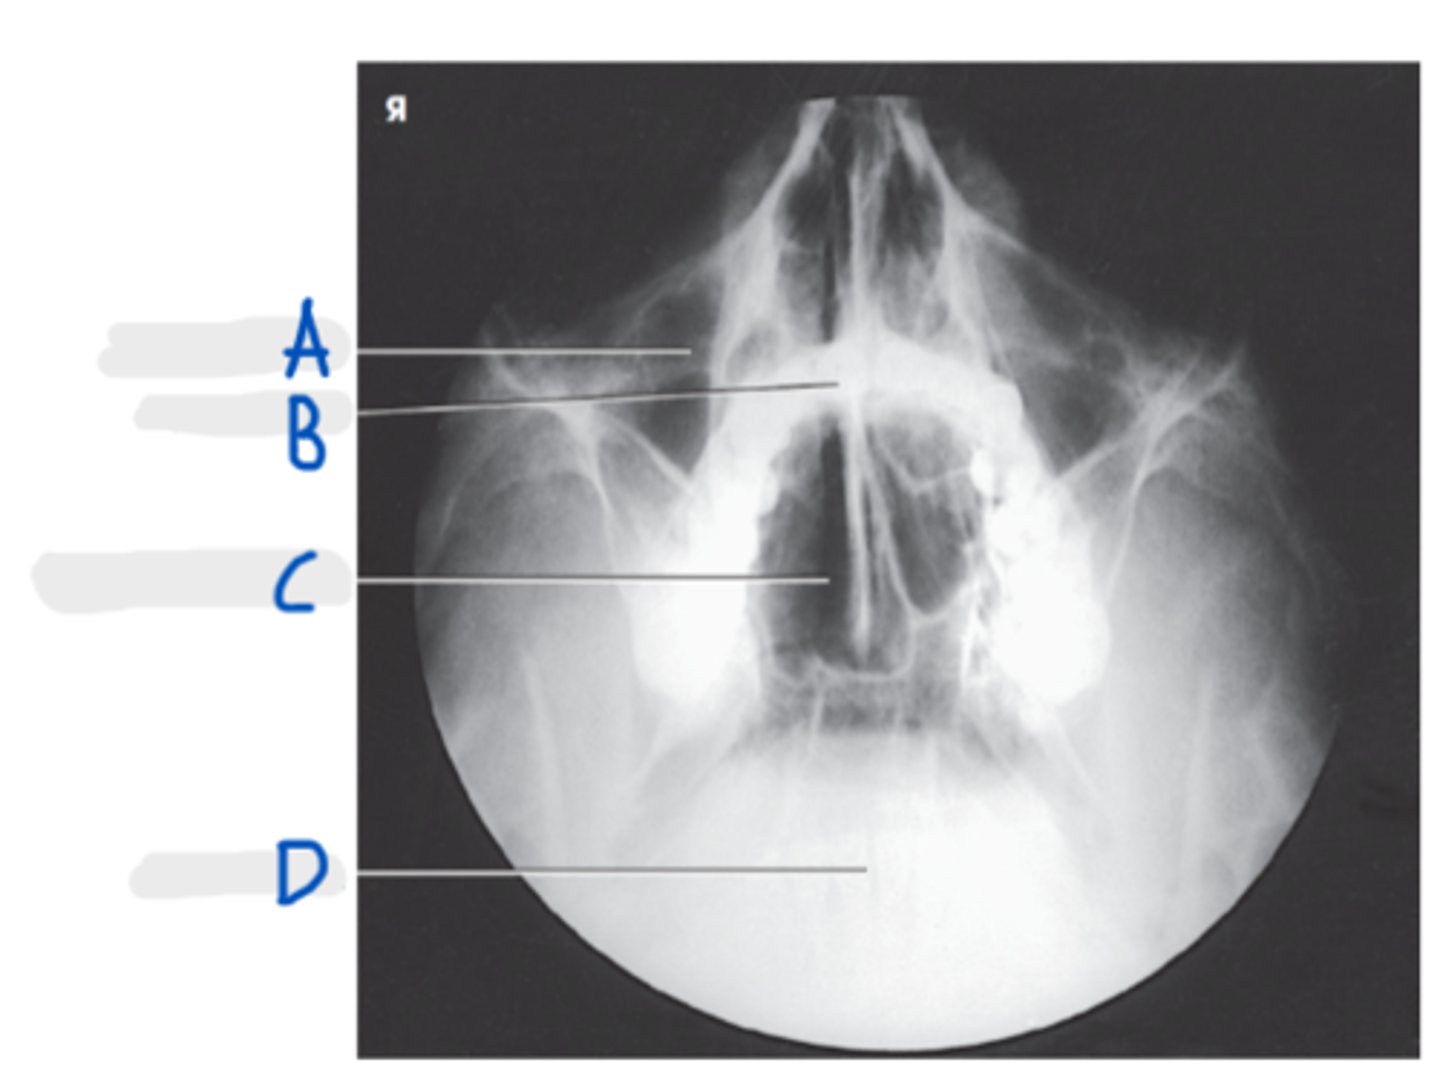

Frontal Sinuses

A

Ethmoid Sinuses

B

Maxillary Sinus

C

Petrous ridge

D

Mastoid air cells

E

PA axial (Caldwell Method)

What projection is this?

CR exits the nasion & 15 degree caudal angle

What is the CR for PA axial (Caldwell Method)?

OML perpendicular to IR

What line should be perpendicular to the IR for a PA axial (Caldwell Method)?

Interpupillary line (IPL)

What line is parallel to the IR for a PA axial (Caldwell Method)?

Frontal and Ethmoid

What sinuses are clearly demonstrated on the PA axial (Caldwell Method)?

Lower 1/3 of orbits

Where are the petrous ridges located in a PA axial (Caldwell Method) radiograph?